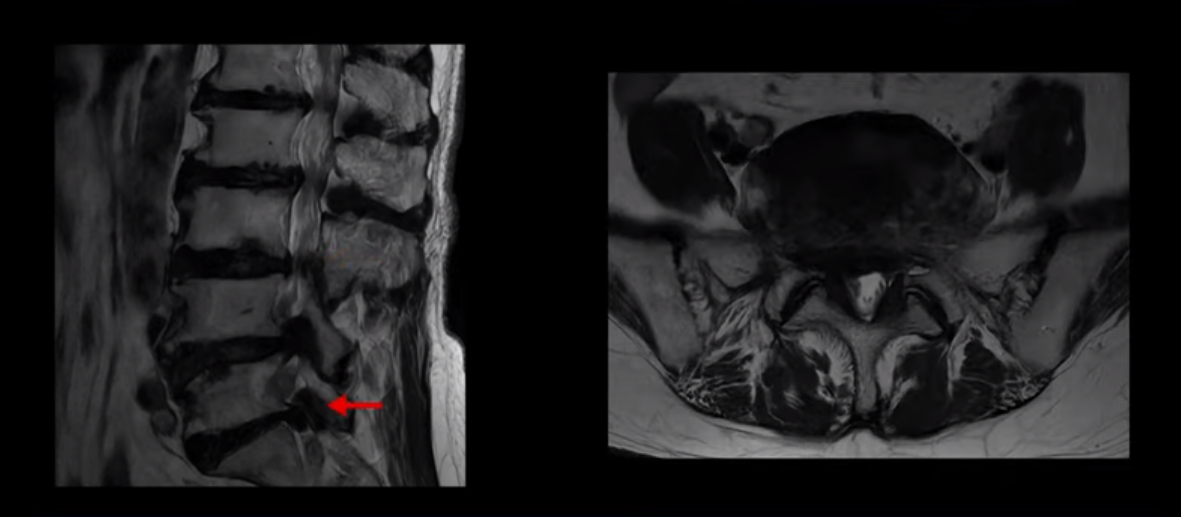

이 환자분은 MRI로 보면 허리 여러 마디가 신경이 매우 심하게 눌려 보이는 분입니다. 이분 MRI를 보면서 간단히 설명해 드린 후 어떻게 이렇게 신경이 심하게 눌린 환자분이 수술 없이 근육신경재활치료로 좋아질 수 있는지, 다리가 아파 걷지 못하는 환자가 어떻게 안 아프고 잘 걸을 수 있게 되는지, 10년 동안 괴로웠던 양 발의 시린 증상은 어떻게 사라질 수 있는지, 치료는 어떻게 하는지 자세히 설명 드리겠습니다.

MRI 보시면 (2-8) 허리의 5마디가 전부 다 심하게 퇴행되어 있습니다.

5마디 전부 다 심한 중심성 협착이 있습니다.

4번 5번,

5번 6번

이렇게 모두 다 심하게 막히는 경우는 드문데요. 또한 오른쪽, 왼쪽 신경이 빠져나가는 추간공도 다 심하게 막혀있습니다.

오른쪽, 왼쪽 이렇게 신경 구멍들이 다 좁아지고 신경이 눌리니까 양쪽 다리가 발바닥까지 아파서 걷기 어렵고 양쪽 발이 10년 넘게 시린 겁니다. 당연히 수술해서 눌린 신경을 풀어줘야 한다고 들으셨는데요. 이런 환자분을 어떻게 수술 없이 치료할까요? 지금부터 설명해 드립니다.